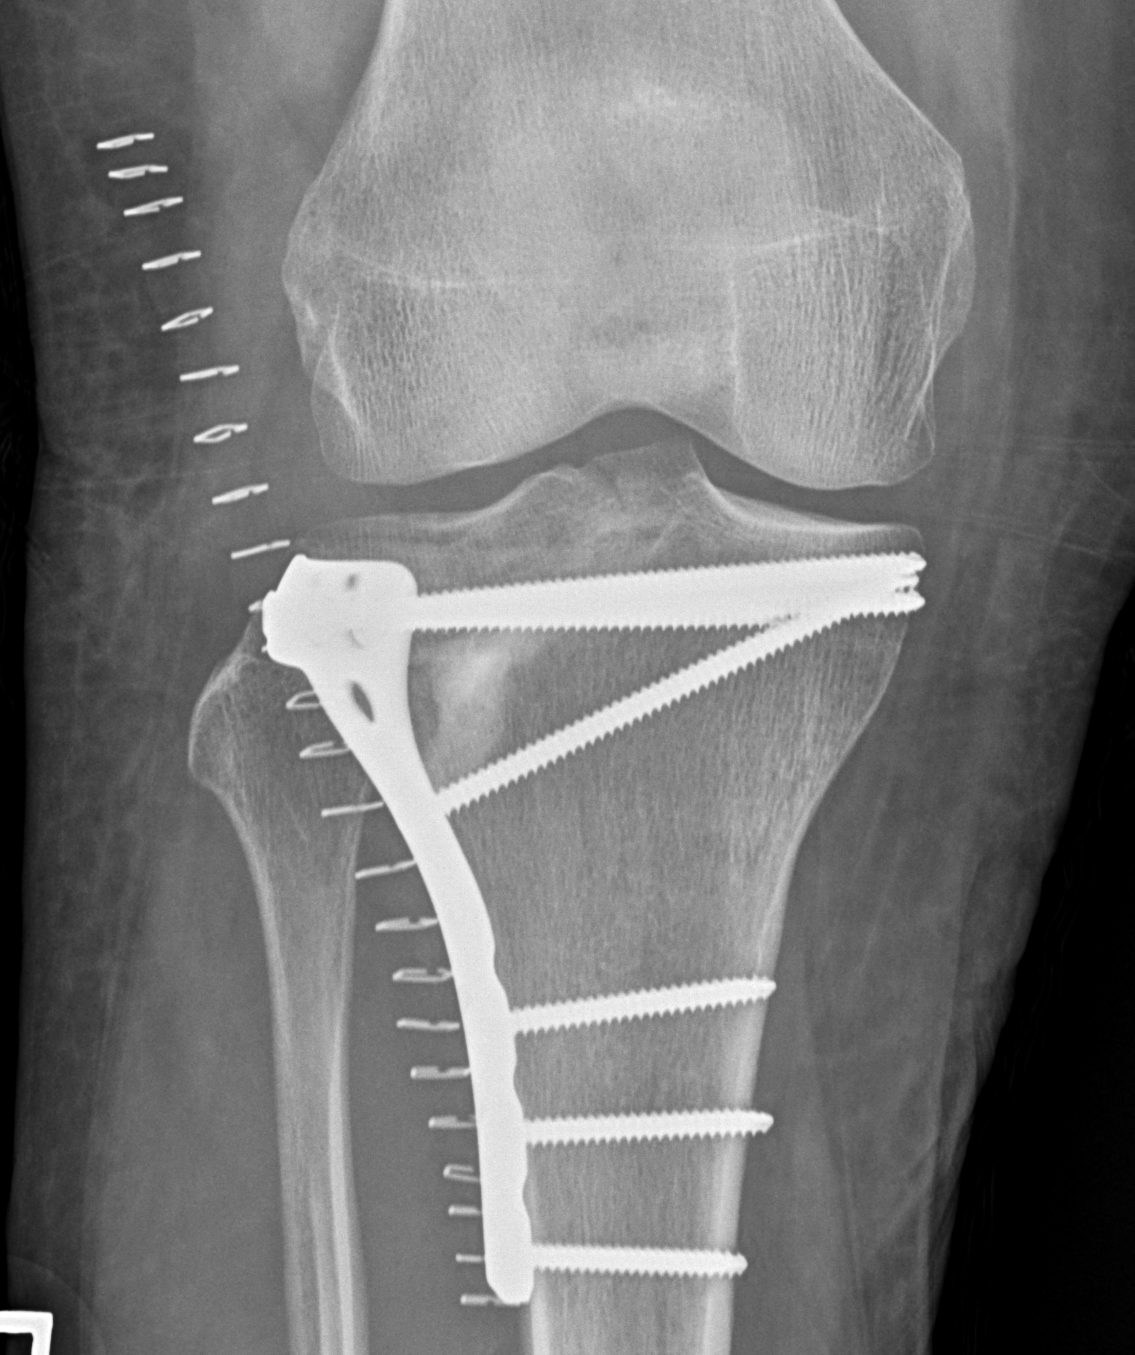

1. Medial and Lateral Plating

Technique

- depends on which of the three columns affected

- anterolateral approach for lateral column

- posteromedial appraoch for medial / posterior column